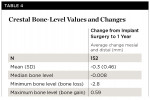

Radiographs were available for 152 implants. The average change from implant surgery to 1-year follow-up was -0.3 mm ± 0.46 mm. No significant differences were seen between the mesial and distal aspects, so they were combined in Table 4, which provides a summary of crestal bone-level values and changes.

Subjects were categorized into groups based on the change in bone level from implant surgery to 1-year follow-up. Most of the subjects (>90%) showed either no bone remodeling or less than 1 mm bone loss. Two subjects (1.3%) had bone gain.Crestal bone-level changes by category are presented in Table 5.